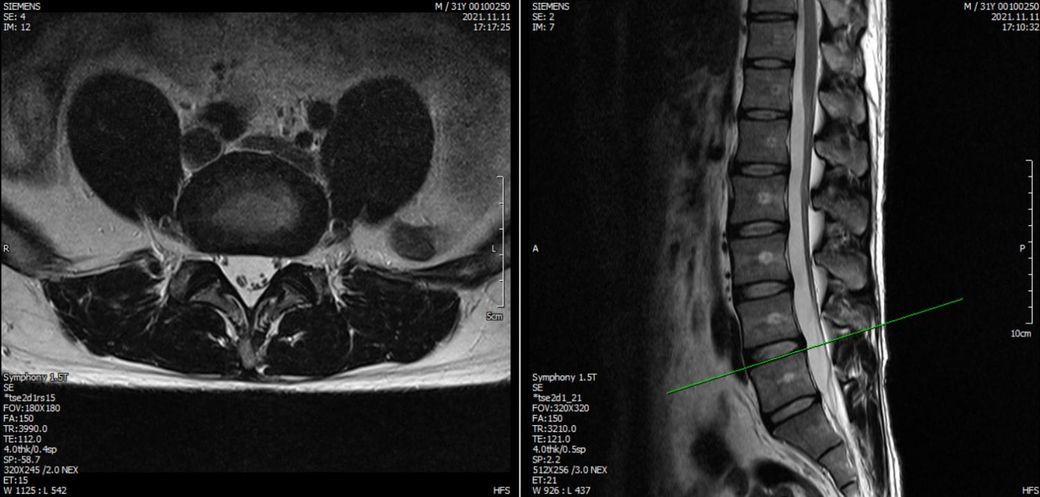

21년도와 24년도 각각 찍은 L spine 사진입니다.

21년도에는 좌측 하지 경미한 저림으로 촬영했었는데 영상으로는 허리가 건강한상태라고 했었습니다.

2021년 영상